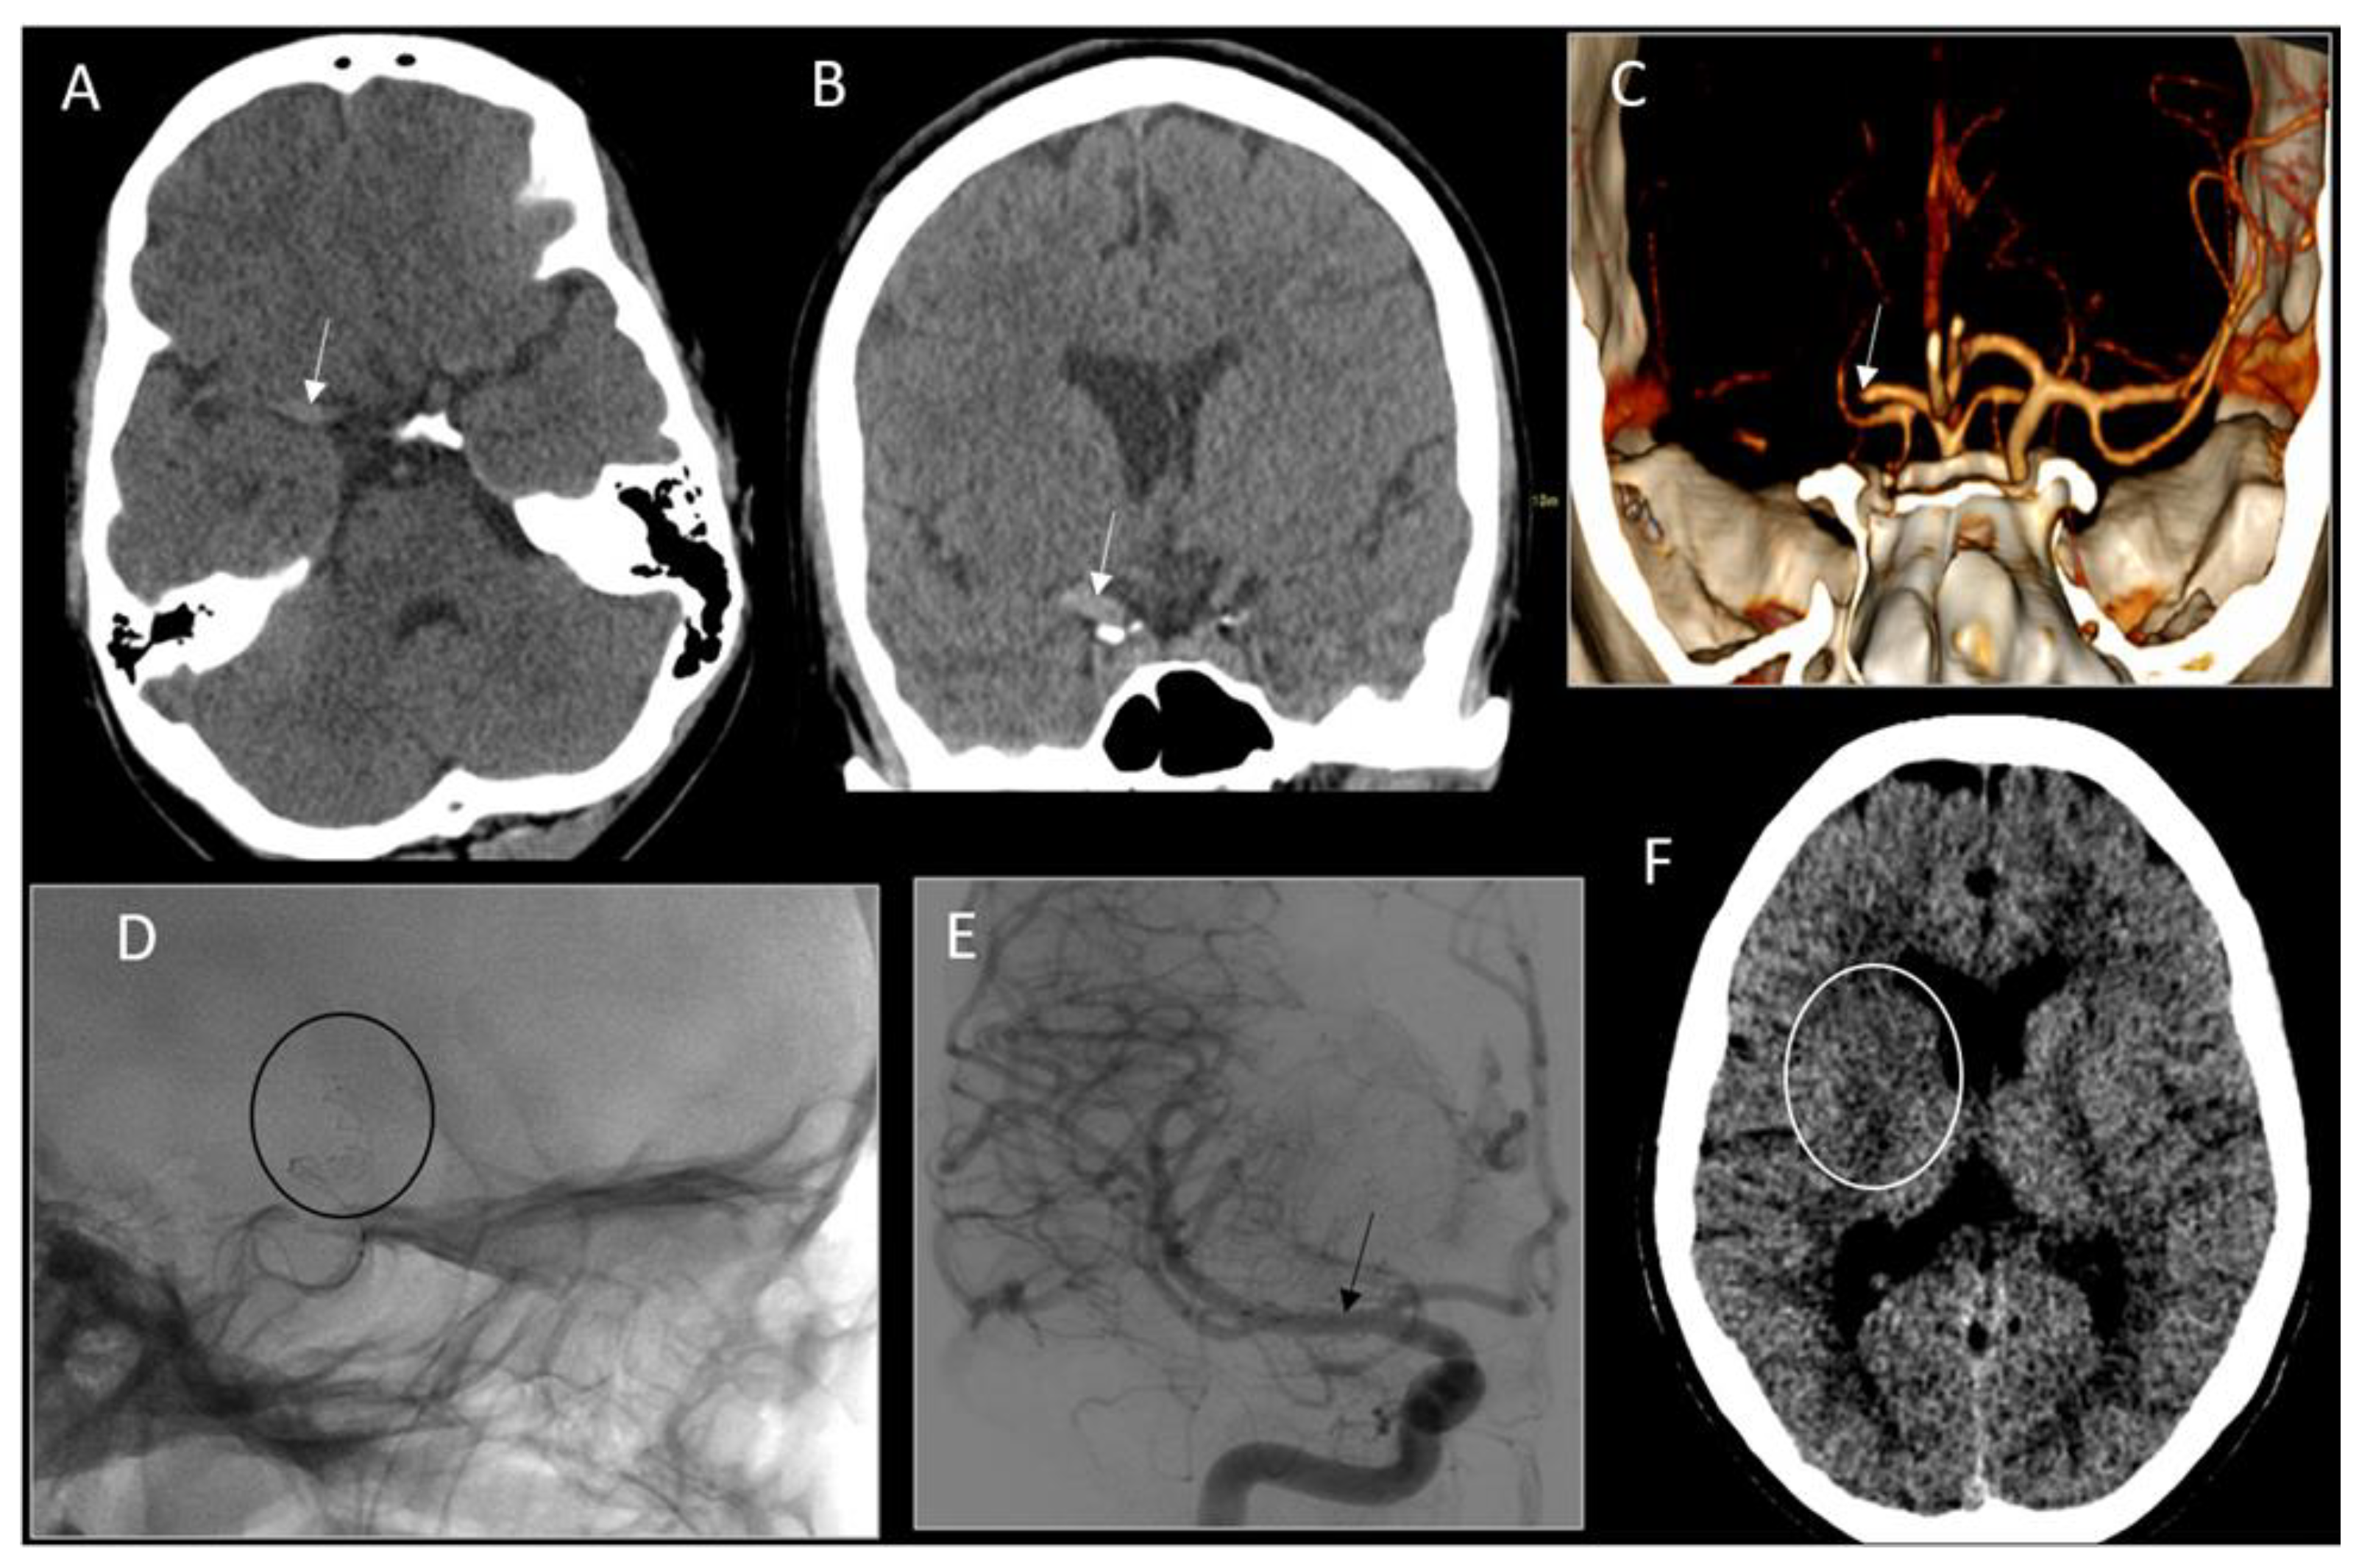

2. Case Report